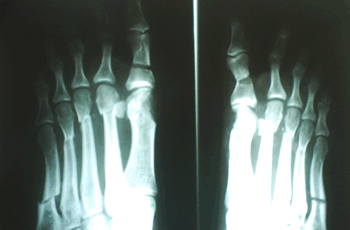

Caso 3: Hallux Valgus del Adulto

Ambos pies operados en el mismo acto quirúrgico.